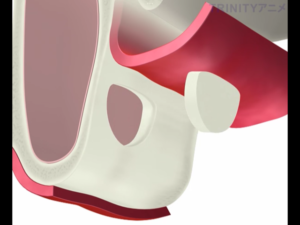

歯茎を切開し、副鼻腔につながる骨を一部削除します。

副鼻腔内の粘膜を破らないように慎重に上方に持ち上げていきます。

それによってできた副鼻腔内の空洞に人工骨を填入します。

骨を盛り上げた部分にインプラントを埋入します。

インプラントの上にドーム状に広がっているのがサイナスリフトを行い填入された人工骨です。